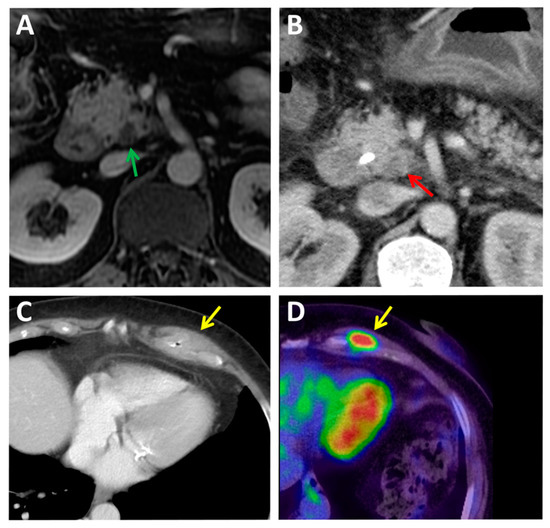

2.4. PET Hybrid Imaging

3.2. The Current Status of Immuno-PET in PDAC